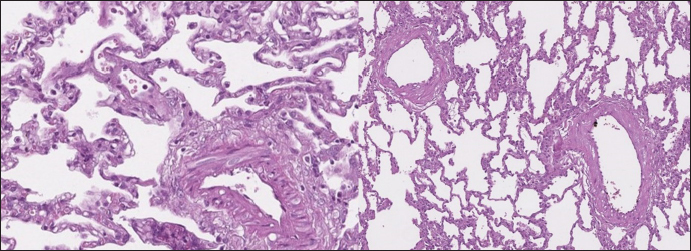

Clinical signs included progressing dyspnea, acute dyspnea, chronic cough, weakness, lameness, cyanosis, and syncope. Chest radiographs obtained on the day of presentation with symptoms showed a diffuse interstitial unstructured pattern with loci of alveolar pattern, cardiomegaly, and in some cases, with left atrial enlargement (Fig. 1).

Fig. 1. Lateral thoracic radiographs of 2 dogs. Left one—RHF group, right -sPCH. Both presented with unstructured interstitial and local alveolar patterns.

In dogs with RHF, with both Masson’s trichrome and hematoxylin and eosin staining, we found wide fields of pulmonary fibrosis, arterial thickening due to tunica media proliferation, and plexiform vascular lesions with signs of revascularization. The dog with pneumonitis showed chronic interstitial histiocytic pneumonia (Fig. 3).

In the sPCH group, we found zones of multifocal mild-to-moderate alveolar septa thickening with numerous capillary proliferation with signs of congestion. Endothelial cells were flattened, but had no signs of anisocytosis or anisokariosis. The growing capillaries expanded in pulmonary tissue, forming nodules and web-like anastomosis with bizarre vessel proliferation which affects zonal bronchi and arteriolas (Figs. 4 and 5).

Fig. 4. sPCH group. Left (dog)—portions of alveolar septae with duplicated capillaries and capillaries proliferation into arterial walls. Right (cat)—less prominent septal alteration, significant arterial walls capillary proliferation. Stained with H&E.